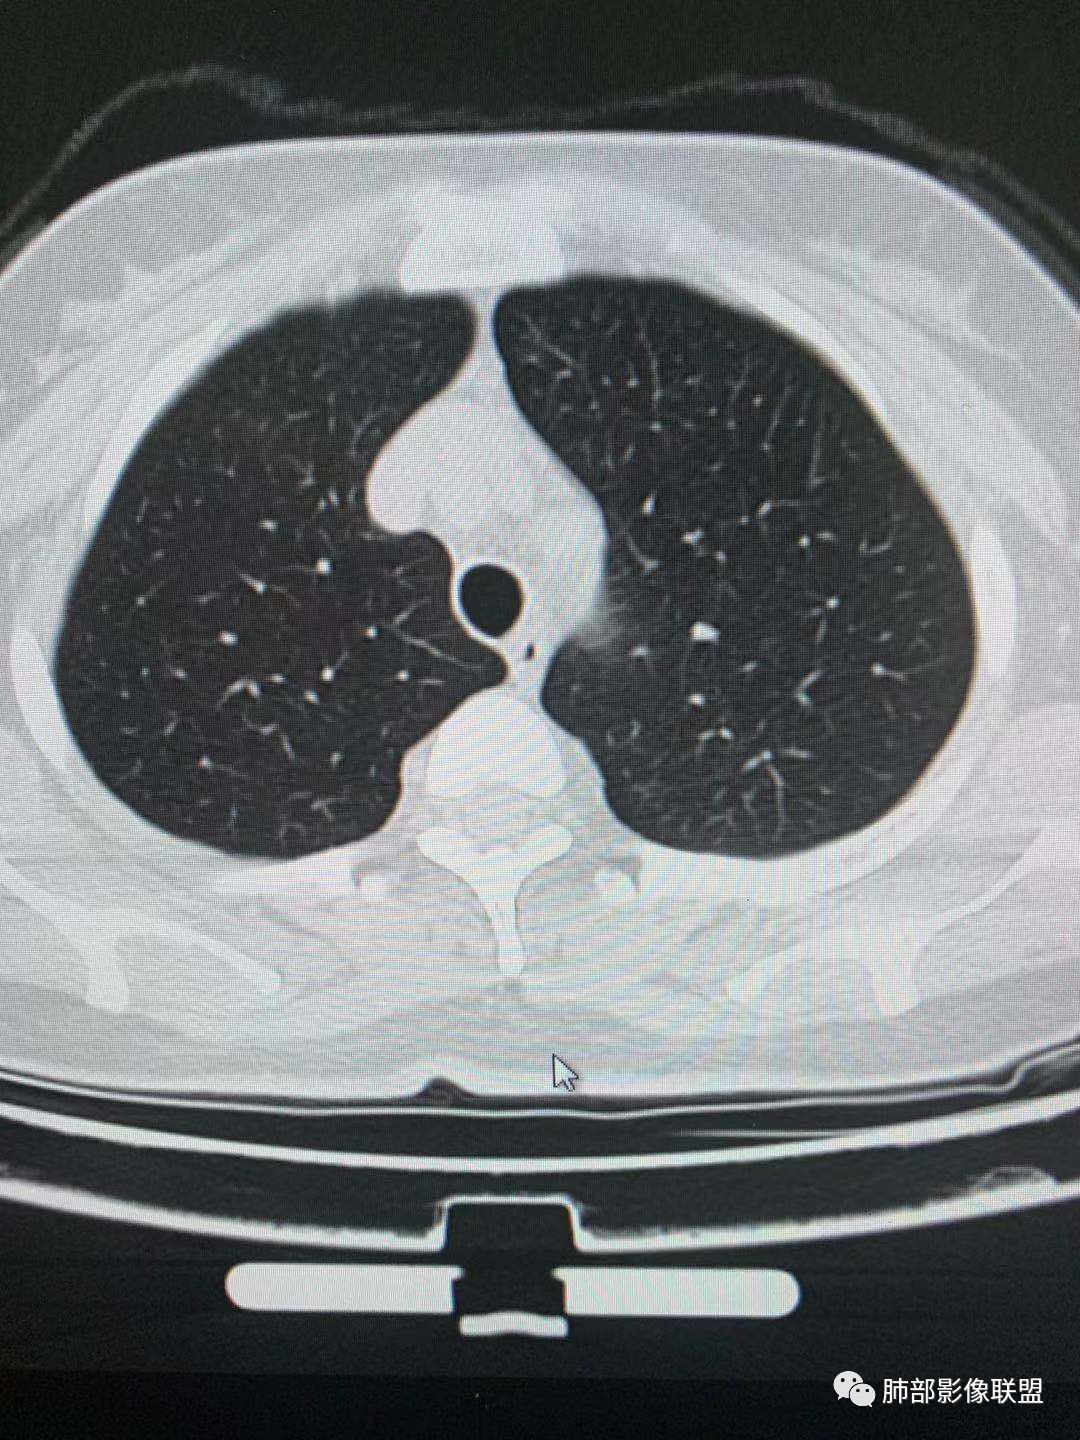

肺磨玻璃结节观察步骤

A

1.密度(纯磨玻璃pGGO、混合磨玻璃mGGO)

2.边界(是否清楚,清楚GGO偏向肿瘤,模糊GGO偏向炎性病变)

3.看边缘及内部征象(有无分叶、毛刺、血管集束征、空泡征、支气管征、胸膜凹陷征)

4.如果倾向肿瘤性病变,可以测CT值及大小,尤其纯磨玻璃结节,结合结节的高危征象,进一步判断早期肺腺癌的亚型分型。

5.如果倾向炎性病变,建议抗炎治疗后2周后随访复查。